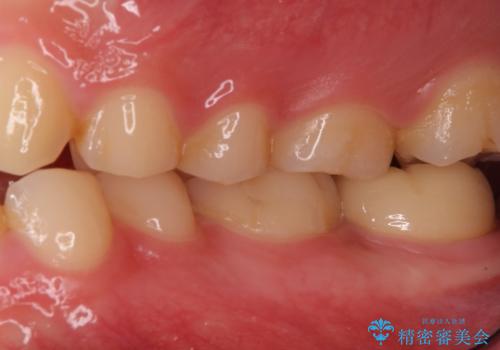

奥歯がしみる 神経を温存する治療

- 左下7 生活歯髄療法:33,000円 仮歯+ジルコニアクラウン:11,000円+121,000円費用は治療当時の料金となります

虫歯が大きくても、今回のように神経を温存することができる場合があります。